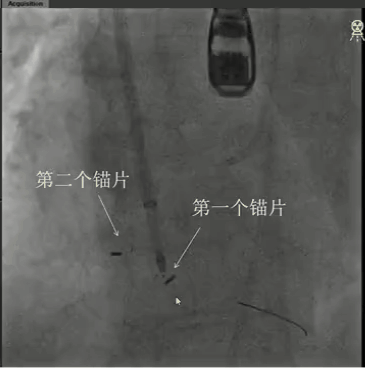

全麻下经右颈静脉入路,在食道超声及放射线引导下,将三尖瓣导丝输送导管经三尖瓣指引导管送至右心室,定位三尖瓣瓣环穿刺位点。穿越导丝连接高频发生器穿刺三尖瓣环(图2),在三尖瓣瓣环上植入一对锚片。通过缩短两个锚片之间的距离折叠三尖瓣瓣环,并通过3D-TEE、2D-TEE确认瓣环折叠及三尖瓣反流情况,最终实现三尖瓣瓣环的二瓣叶化(视频1),从而降低因瓣环扩大、瓣叶关闭不全产生的三尖瓣反流。

视频1:a:锚片锚定三尖瓣瓣环,b:三尖瓣后瓣折叠